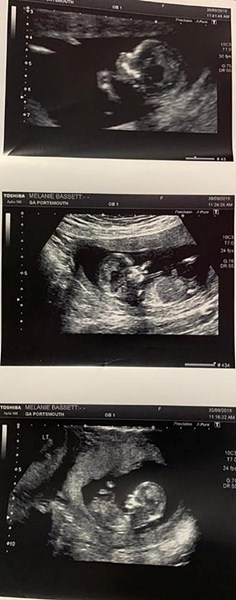

В едната матка тя износила близнаци, а във втората – третото дете

Британка с вроден порок, заради който в организма ѝ се формирали две матки, роди тризнаци. В едната матка тя износила близнаци, а във втората – третото дете, съобщи вестник Daily Mail, цитиран от БГНЕС.

32-годишната Мелани Басет вече има две деца. Но когато лекарите ѝ обявили за тройната бременност, тя била шокирана. Мелани научила за своята патология през 2016 година, когато била бременна с дъщерята си, първото ѝ дете. След две години тя забременяла още веднъж, тогава двойката имала син.

Според лекарите шансът една жена с две матки да износи и роди тризнаци се оценява като един на милион. Басет станала първата жена в Обединеното кралство, която направила това.